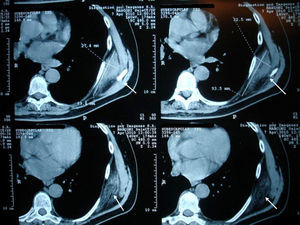

Clinical CasesCase 1A 73-year-old patient with a history of osteoarthritis in their hands presented with pain in the left scapular region of 3 months duration, which was exacerbated by physical activity, referring the pain to the scapular area of the shoulder after movement. Physical examination found a hard consistency, elastic, painless mass approximately 7cm in diameter in the left subscapular region. Ultrasonography of the affected region reported a solid mass of the chest wall, which was below the serratus anterior (Fig. 1). CT scan showed a unencapsulated occupying mass with density similar to muscle, mixed with adipose tissue bands in the left infrascapular region of 8.8 by 2.4cm (Fig. 2). Hematological and biochemical analyzes were normal. The orthopedics department suggested excision of the lesion, but the patient refused surgery. A control CT scan 2 years later showed no changes.